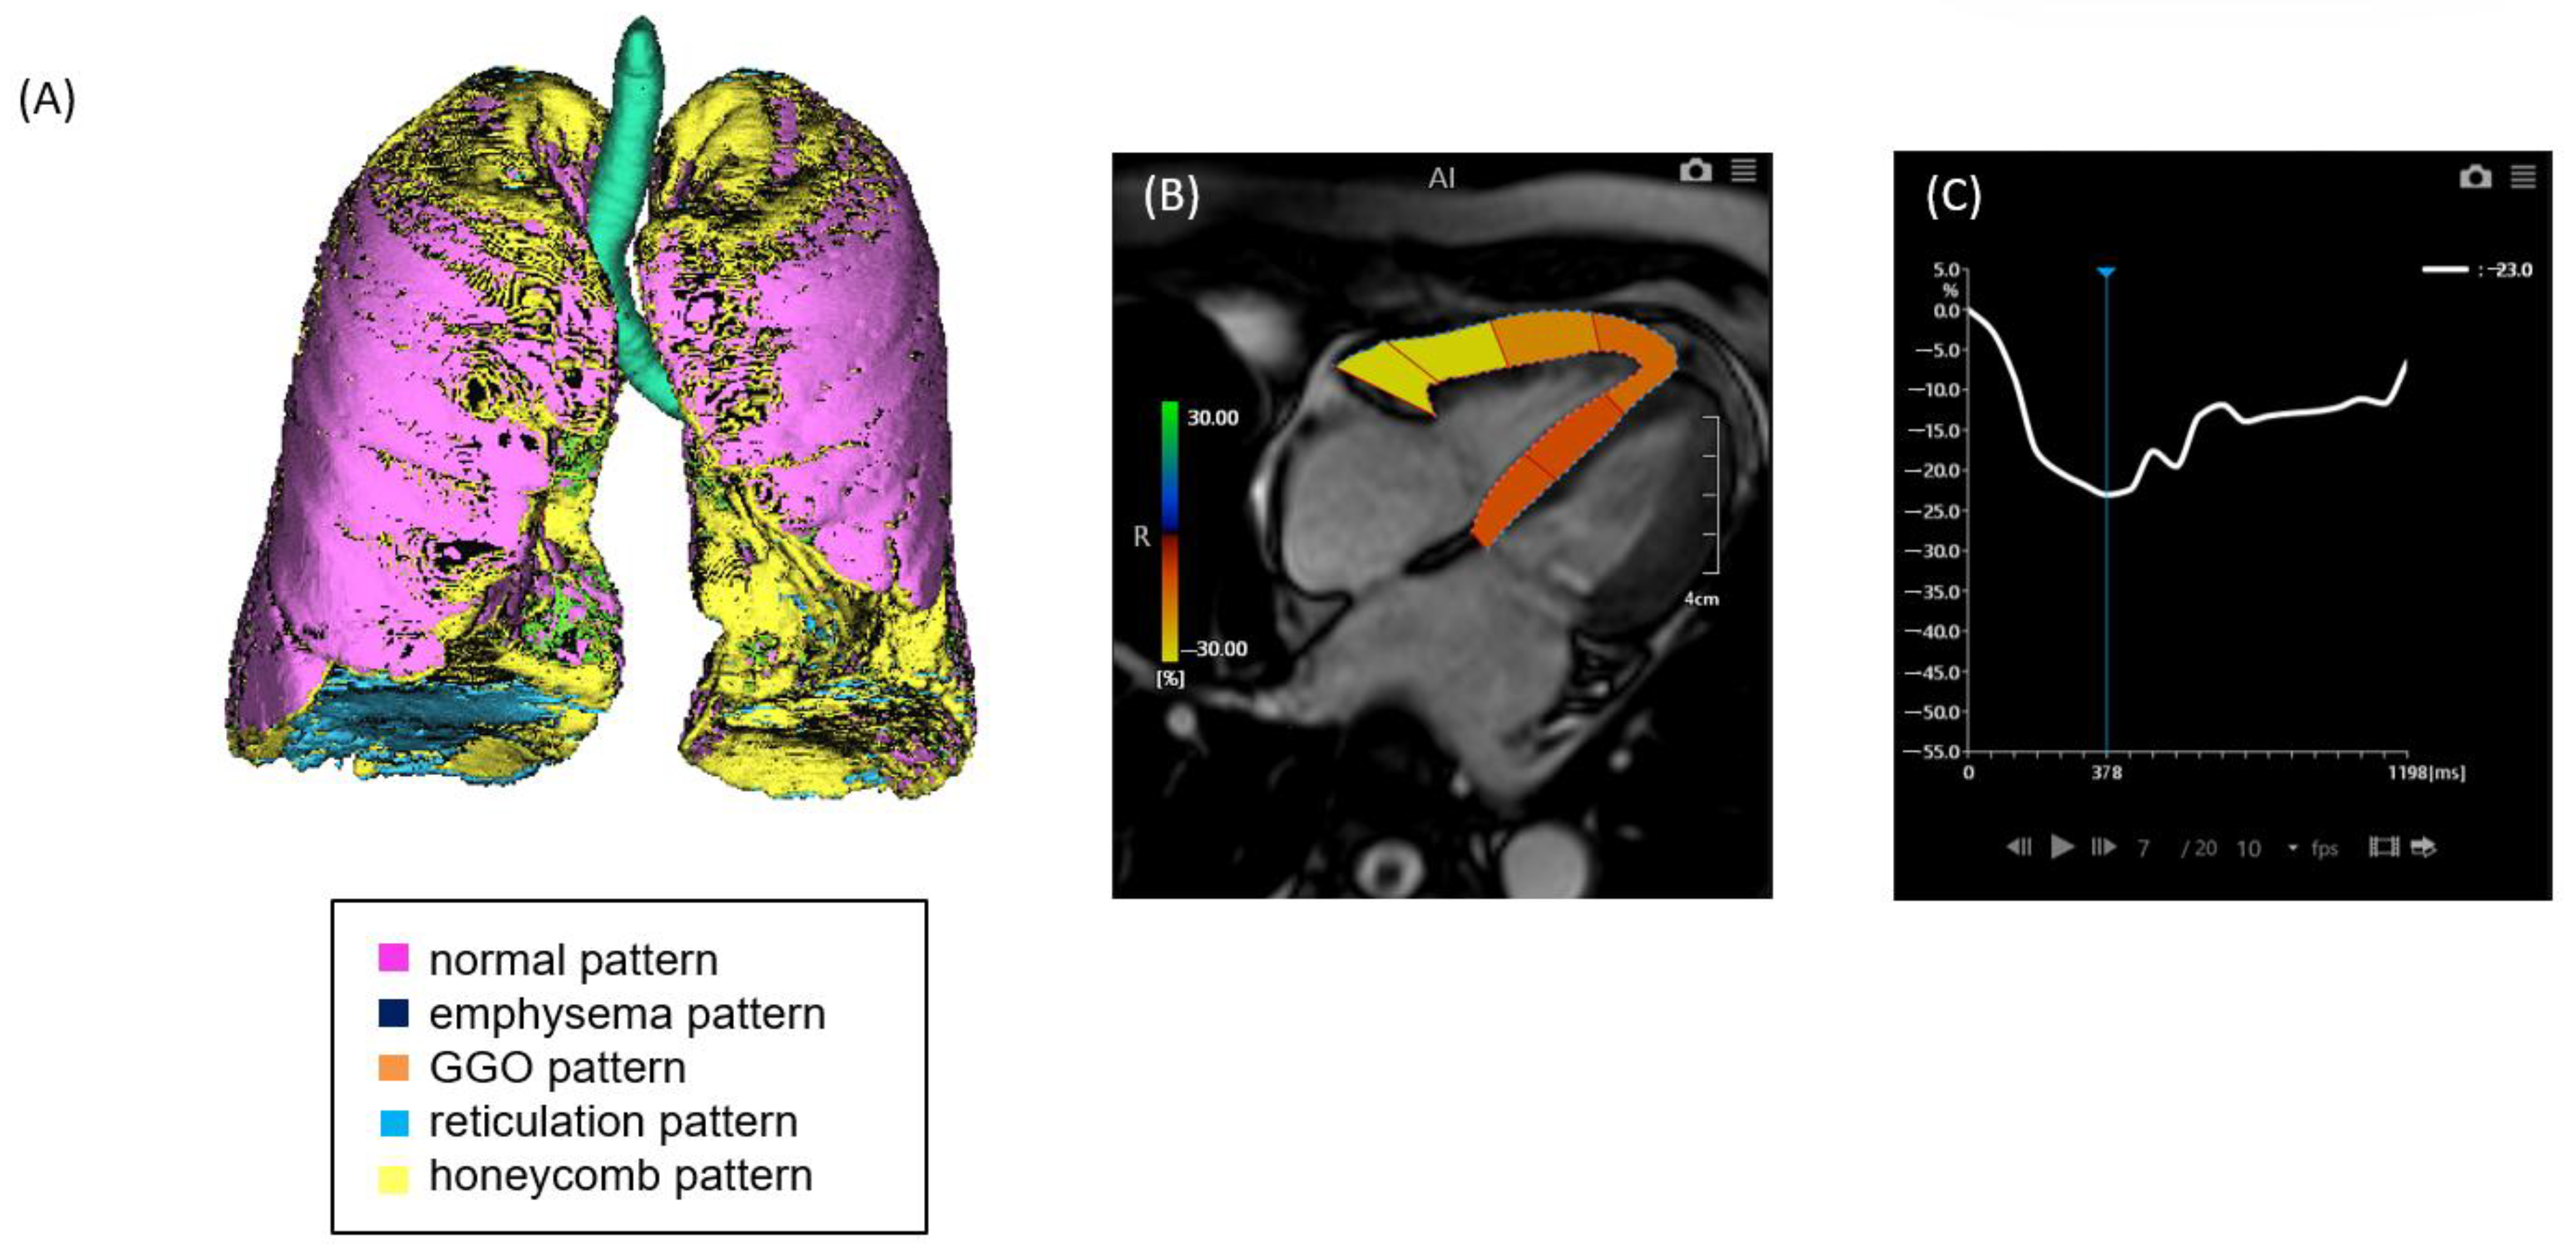

Figure 1. A case of ILD with mild pulmonary fibrosis and preserved right ventricular (RV) strain. (A) Quantitative CT-based 3D reconstruction of lung parenchymal patterns. Normal lung parenchyma (pink), emphysema (dark blue), ground-glass opacity (GGO, orange), reticulation (light blue), and honeycombing (yellow) are segmented. (B) Cardiac MRI showing right ventricular strain analysis using feature tracking. (C) Strain–time curve of the right ventricle showing preserved peak longitudinal strain (−23.0%).

2.2. CT Image Acquisition and Analysis

Non-contrast chest computed tomography (CT) scans were obtained during full inspiration in the supine position using multidetector CT scanners (Aquilion 64, Aquilion ONE 320, or Aquilion Precision 160; Canon Medical Systems, Japan). The slice thickness was 0.5 or 1.0 mm. The median interval between CT and RHC was 71 days (mean, 88.5 days; range, 0–325 days). CT data were analyzed using the GHNC system, which classifies lung parenchyma into six categories—normal (N), emphysema (E), ground-glass opacity (GGO, G), consolidation (C), reticulation (R), and honeycombing (H)—based on local histogram features and CT attenuation values [9,10]. These categories were predefined using datasets from healthy individuals and patients not included in the current study. The system automatically calculated the volume of each category and the total CT lung volume (CTLV), displaying the results as color-coded overlays. Volumetric data for each category were expressed as percentages of the CTLV. The diseased lung area was defined as the sum of all non-normal parenchymal patterns, including GGO, honeycombing, reticulation, emphysema, and consolidation (Figure 1 and Figure 2). In this study, the extent of fibrosis was quantitatively assessed using the percentage of diseased lung area—defined as the sum of GGO, reticulation, honeycombing, consolidation, and emphysema—relative to the total CT lung volume (i.e., expressed as a percentage of the entire lung). This quantitative measure was used as a surrogate marker for the stage of pulmonary fibrosis.